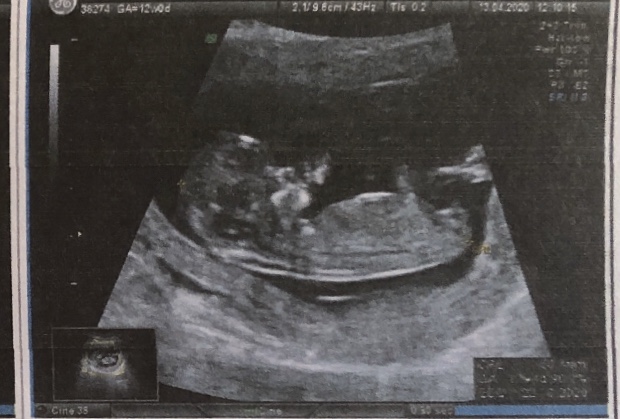

Вчера прошли первый скрининг, очень волновалась, но все в порядке 🙏 все риски низкие)

Надеялась, что уже смогут сказать пол, но врач пока не стала утверждать) Решила прикрепить фото с узи, может кто-то глазастый и опытный разглядит)

Девочка ,половой бугорок параллельно позвоночнику

И ничего мальчикового у вас не торчит)

Определяют по половому бугорку, потому ни к чему говорить о чем-то там между ног. Это между ног у всех одинаковое на таком сроке. Есть разница по углу наклона. У девочек прямо, у мальчиков примерно 90 градусов вверх. Т.к. тут я ничего не вижу на 90 вверх, зато вижу параллельно позвоночнику-значит девочка.